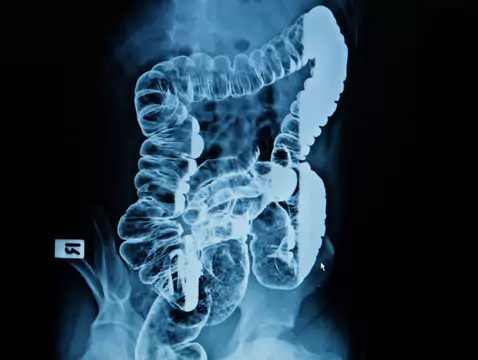

Nowotwór jelita grubego jest nowotworem występującym w obrębie: okrężnicy, zgięcia esiczo-odbytniczego oraz odbytnicy. W 90-95% przypadków zachorowanie na nowotwór złośliwy jelita grubego jest...

WHO opublikowała badania zgodnie z którymi spożycie czerwonego oraz wysoko przetworzonego mięsa może mieć związek z zachorowalnością na raka jelita grubego.